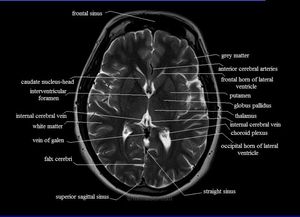

Neuroradiology